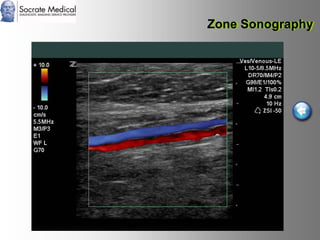

Il documento presenta la tecnologia della zone sonography, che promette una rivoluzione nel campo degli ultrasuoni, superando i limiti dei sistemi tradizionali grazie a metodi di acquisizione dati più veloci e una gestione delle informazioni migliorata. Questa tecnologia consente una maggiore definizione dell'immagine, una riduzione degli artefatti e un'ottimizzazione del processo diagnostico, con vantaggi in termini di tempo e costi. Inoltre, il channel domain processing e la zone speed technology offrono applicazioni avanzate e miglioramenti nella sicurezza diagnostica.